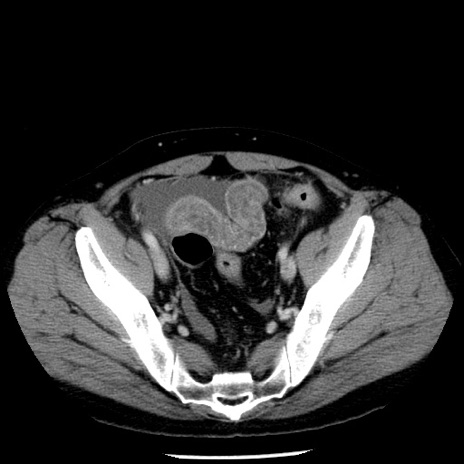

冠状断像

【症例】40歳代男性

【現病歴】2日前から胃痛あり。徐々に周期的な激痛に変化した。本日になっても激痛があるため受診。

【身体所見】意識清明、BT 38-39℃台あり、腹部:膨満、やや硬、右下腹部に圧痛あり。

【データ】WBC 8500、CRP 23.26